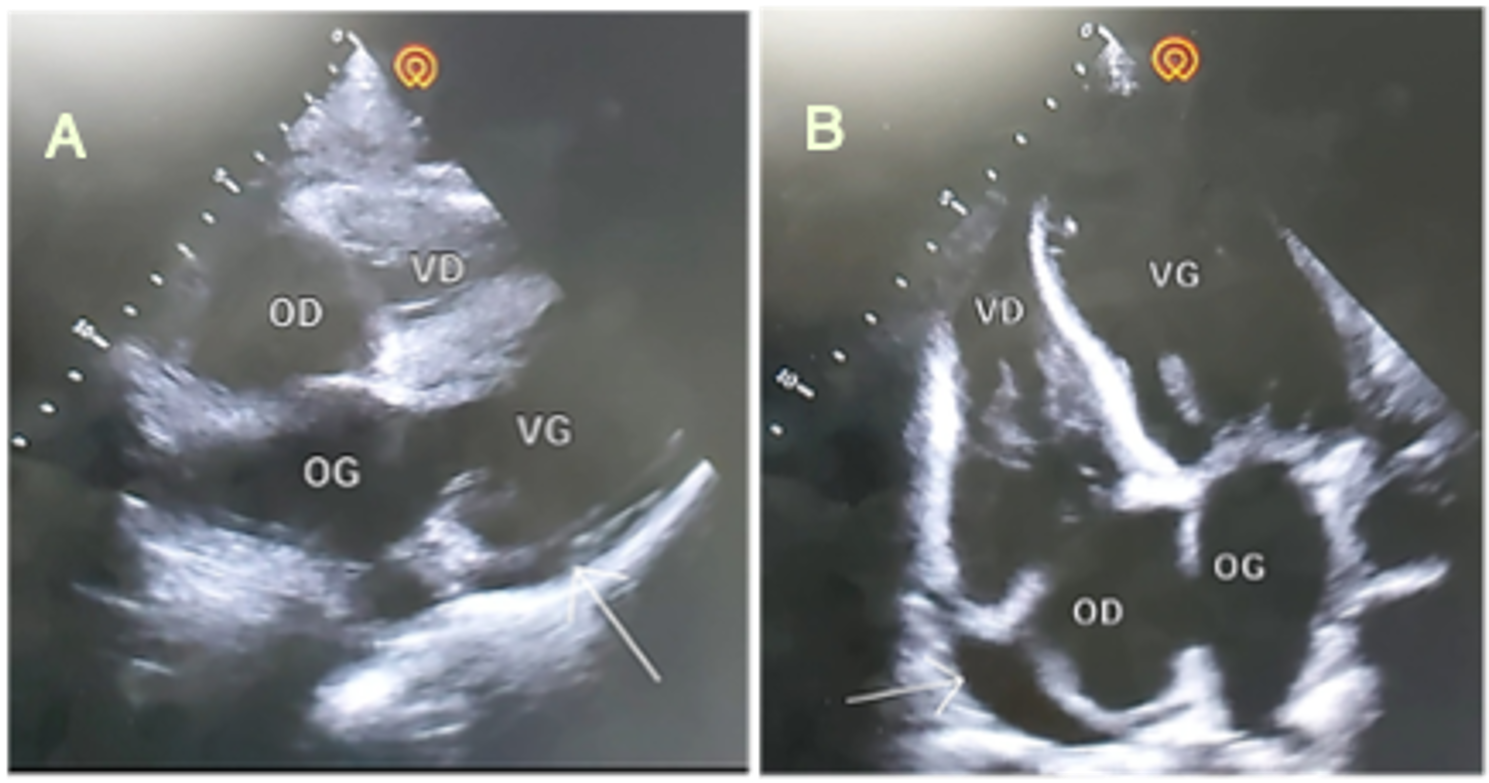

Trans Thoracic Echocardiography (TTE) revealed a 14-mm circumferential pericardial effusion of moderate size, with no right chamber involvement and a left ventricular ejection fraction (LVEF) of 68% ( Figure 2.). Biological tests revealed an inflammatory syndrome (CRP 58 mg/L) and negative troponin at 21 ng/dL.

Figure 2.Subcortical (A) and apical (B) echocardiographic sections, showing a 14-mm pericardial effusion.